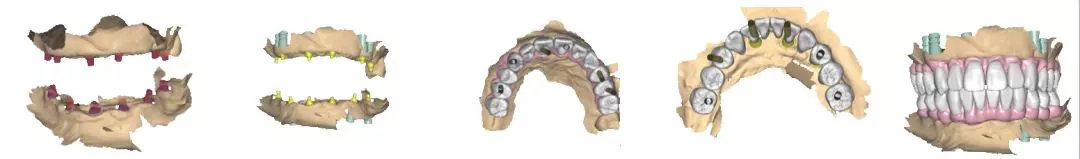

· 制作放射导板,进行数字化导板设计。

· 上下各计划植入6颗种植体。其中14、24种植体倾斜植入,15、25经牙槽嵴顶上颌窦提升植骨,其余牙位无需植骨。

种植体位置设计,可见上前牙唇侧骨量过丰满,需适量去骨。同时上下颌均需要截骨处理。

· 上下颌士卓曼360数字化导板 +预成临时修复体设计图。

· 士卓曼360导板包括:骨支持的基部导板 、牙支持的辅助导板 、就位于基部导板的种植导板 以及就位于基部导板的预成临时修复体组成。

· 上下颌计划行即刻种植,各植入六颗straumann钛锆种植体并行即刻修复。

· 最终修复体采用士卓曼原厂切削纯钛桥架+氧化锆整体桥。